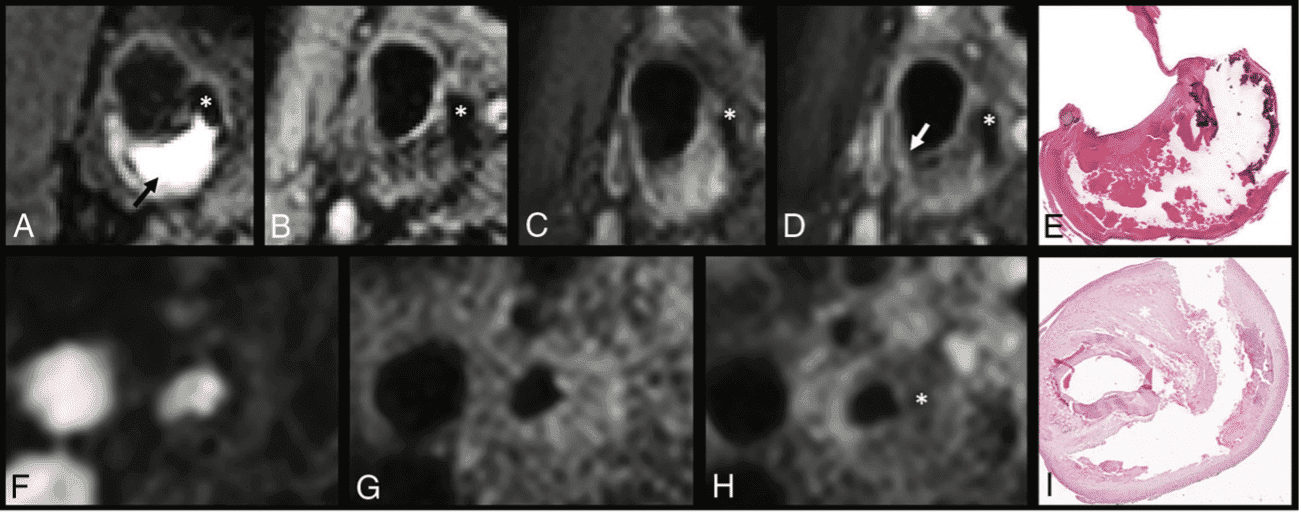

Como regra geral, estudos histopatológicos mostraram que as placas vulneráveis são caracterizadas por cápsula fibrosa afilada ou rota, erosões endoteliais, inflamação, núcleo lipídico / necrótico (“lipid-rich necrotic core” – LNRC), presença de neovascularização e hemorragia intraplaca, destacando-se que a posição do LNRC e do afilamento da cápsula fibrosa estão intimamente ligados ao risco de rotura da placa. As placas estáveis e assintomáticas tipicamente contêm mais tecido fibrótico e calcificações.

As características que definem a vulnerabilidade da placa estão relacionadas à ocorrência de eventos isquêmicos independentemente do grau de estenose, tanto em pacientes sintomáticos quanto em assintomáticos. A presença de hemorragia intraplaca, por exemplo, foi associada a um aumento de seis vezes no risco de evento cardiovascular.

Um estudo prospectivo em pacientes assintomáticos com estenoses moderadas demonstrou que o tamanho do LRNC determinou o risco de futura rotura da superfície da placa, sugerindo que a instauração urgente de terapia antilipêmica pode prevenir a transformação de uma placa estável em uma placa instável. A avaliação anual da placa por RM de alta resolução é útil no monitoramento da terapia, sendo capaz de demonstrar a redução do LRNC e o aumento do conteúdo fibroso, que precedem a redução do volume da placa.